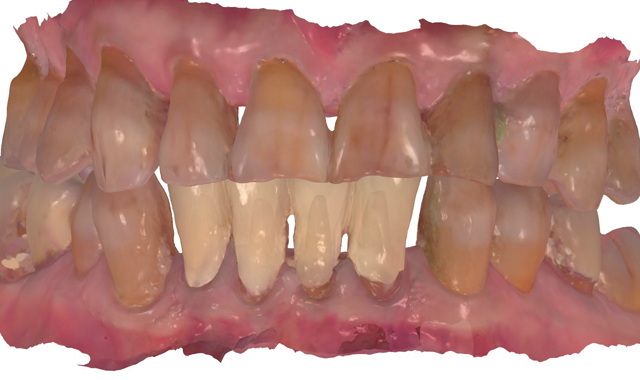

An 88-year-old man presented for restoration of tooth #25, which was fractured and had been endodontically treated (Fig. 1). A thorough intraoral and radiographic examination was performed, which revealed damage to the remaining anterior mandibular teeth incurred over the years as a result of scaling and curettage (Fig. 2). This damage to the

root surface of the lower incisors-which was visible on the radiograph (Fig. 3)-is known as “Riffle-ization.” Described by Dr. Riffle as a technique for removing every last bit of calculus during repeated root scaling, what is now known as “Riffle-izing," ultimately-over the years-changes the shape of the neck of the tooth to resemble an hour glass.

Therefore, based on the clinical and visual evaluation, the preferred treatment would be to restore the fractured #25 with a post and crown and four splinted crowns to restore the anatomy of the four incisors and increase their resistance to both mobility and fracture.